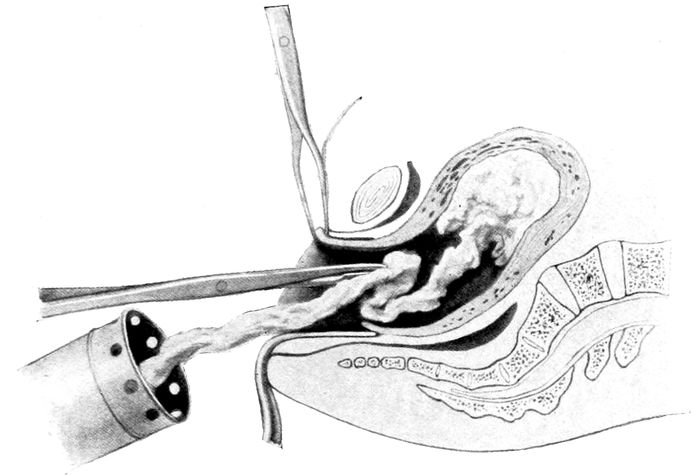

| 87. |

203 |

| 88. |

204 |